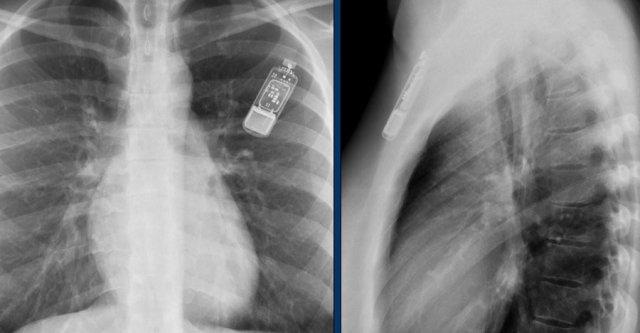

Máy ghi vòng lặp (Loop recorders)

Máy ghi vòng lặp là các thiết bị theo dõi tim có thể cấy ghép, dùng để ghi lại liên tục nhịp tim ở những bệnh nhân có triệu chứng hồi hộp đánh trống ngực hoặc ngất không rõ nguyên nhân.

Các thiết bị này được đặt dưới da.

Những thiết bị này ngày càng được thu nhỏ hơn và không nên nhầm lẫn với ổ đĩa USB.

Máy ghi vòng lặp có nhiều ứng dụng khác nhau, bao gồm theo dõi bệnh nhân có các cơn ngất không rõ nguyên nhân và đánh giá bệnh nhân mắc rung nhĩ, rối loạn nhịp thất hoặc rối loạn dẫn truyền.

Các máy ghi này có thể cung cấp khả năng theo dõi hơn một năm, có thể được kích hoạt bởi bệnh nhân hoặc tự động kích hoạt.

Một ví dụ khác về máy ghi vòng lặp.